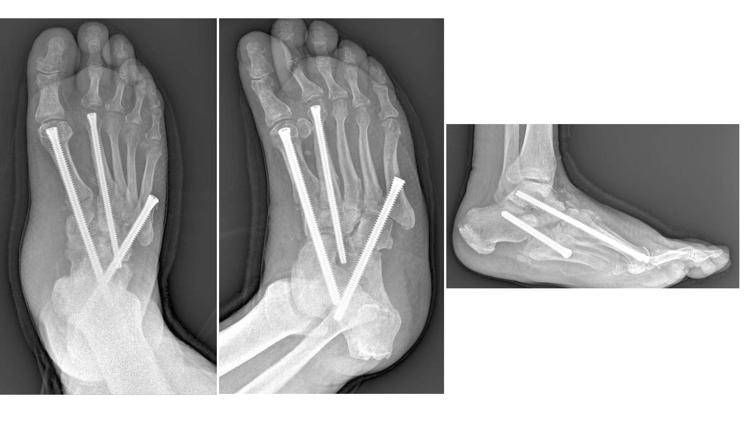

"Sono interventi che mirano a correggere deformità estremamente complesse del piede e della caviglia - illustra Perisano - e che prevedono una serie di procedure chirurgiche (nell'ambito dello stesso intervento), quali osteotomie correttive e successive osteosintesi. Questo consente la ricostruzione di un asse del piede e della caviglia, per permettere al paziente di tornare a camminare (in genere entro un paio di mesi dall'intervento). I pazienti affetti da questa condizione infatti non riescono più a deambulare perché queste deformità comportano alterazioni dell'appoggio, che sottopongono alcune zone del piede, normalmente non deputate a sostenere il carico, ad una pressione eccessiva che a sua volta può portare ad ulcerazioni; queste, nei pazienti diabetici (che spesso sono anche vasculopatici), possono causare infezioni gravi e profonde, che a loro volta comportano un elevato rischio di amputazione".